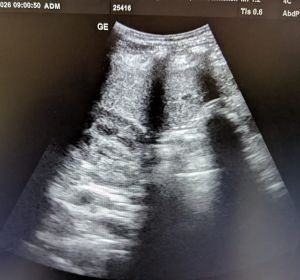

Röntgenuntersuchung